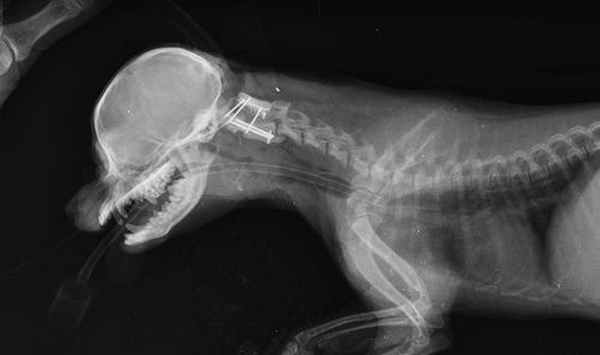

Краниография собаки с вентральной стабилизацией С1-С2.

Интраоперационное - вентральная фиксация спицами Киршнера первого и второго шейного позвонка.